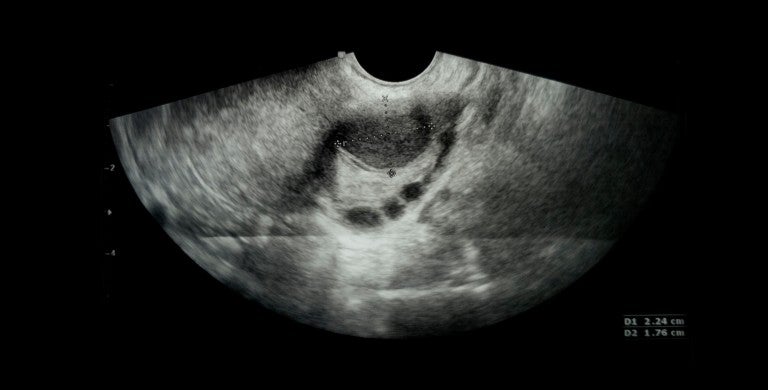

Diagnosis of an ovarian cyst involves a pelvic exam and transvaginal ultrasound (also called ultrasonography). An ultrasound transducer (probe) is inserted into your vagina and used to bounce high-energy sound waves (ultrasound) off internal tissues or organs and make echoes. The echoes form a picture of body tissues called a sonogram.